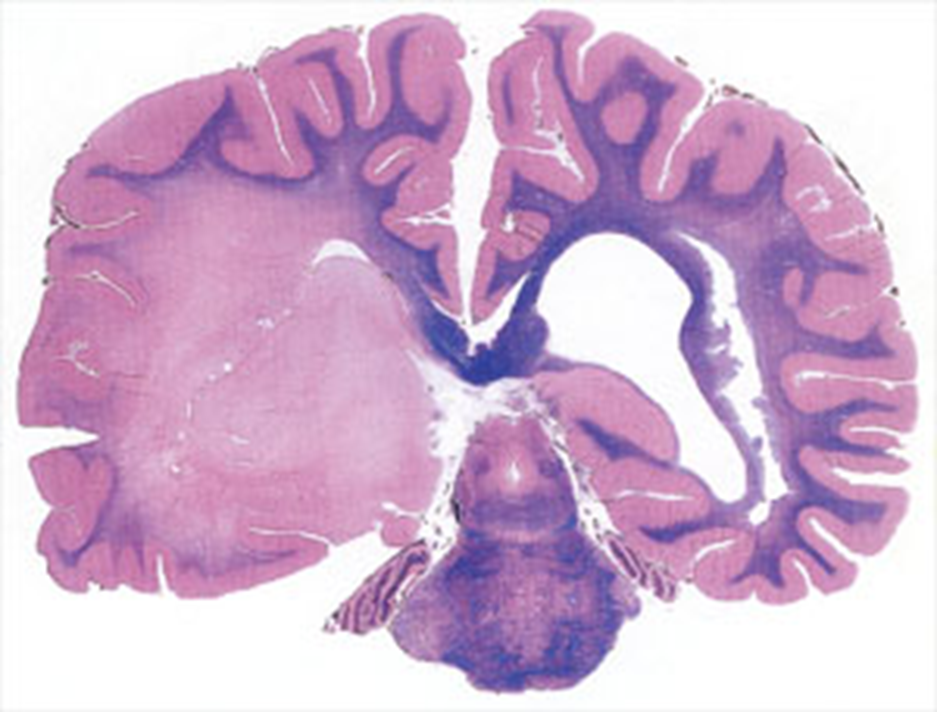

Diffuse Astrocytoma, WHO Grade II

Infiltrating pleomorphic glial cells with increased cellularity

light in color edematous astrocytes

Neoplastic vs normal white matter

Astrocytoma WHO grade 2